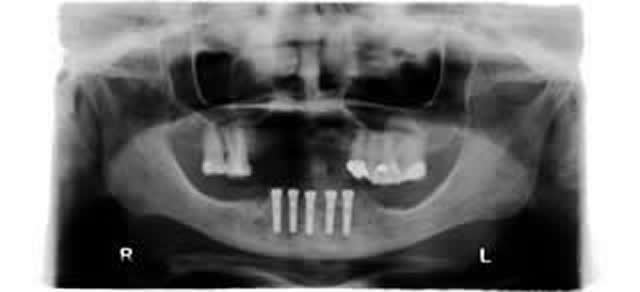

5 implants fixed bar supported lower denture. That's patient's own finger.